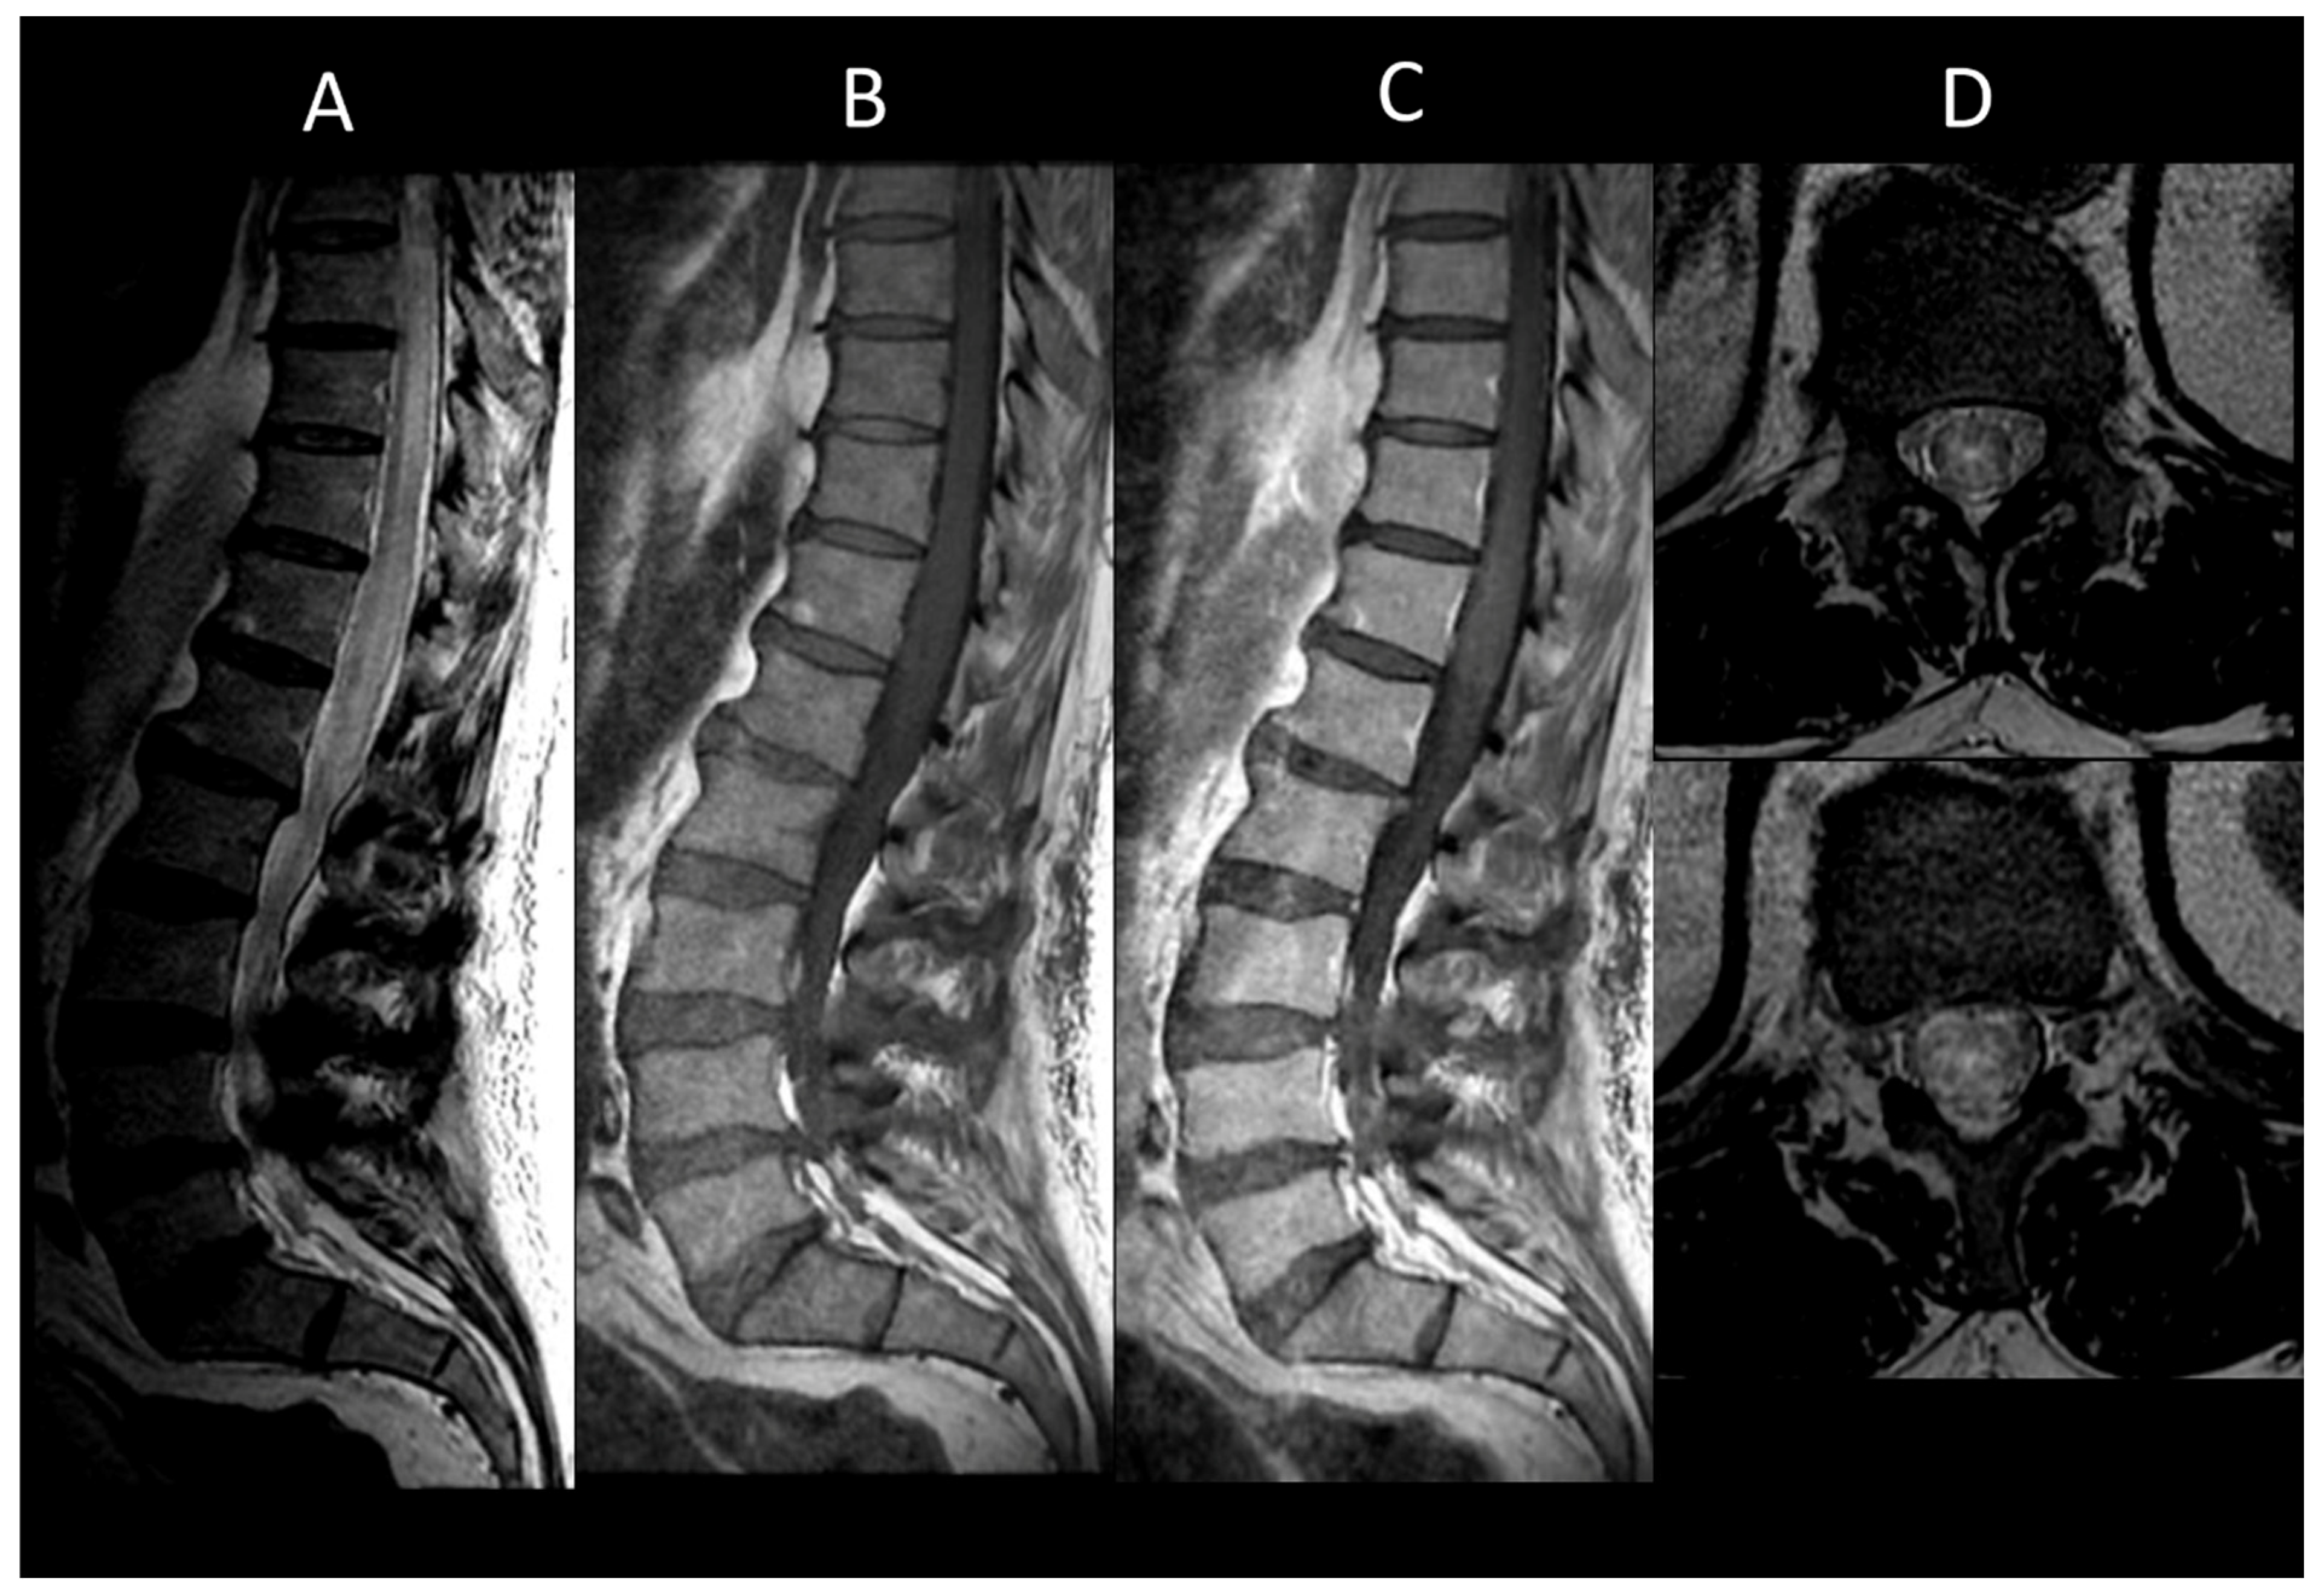

3.2. Degenerative Compressive Myelopathy

3.3. Vascular Myelopathies

3.3.2. Spinal Dural Arteriovenous Fistula

3.3.3. Spinal Cavernous Malformation